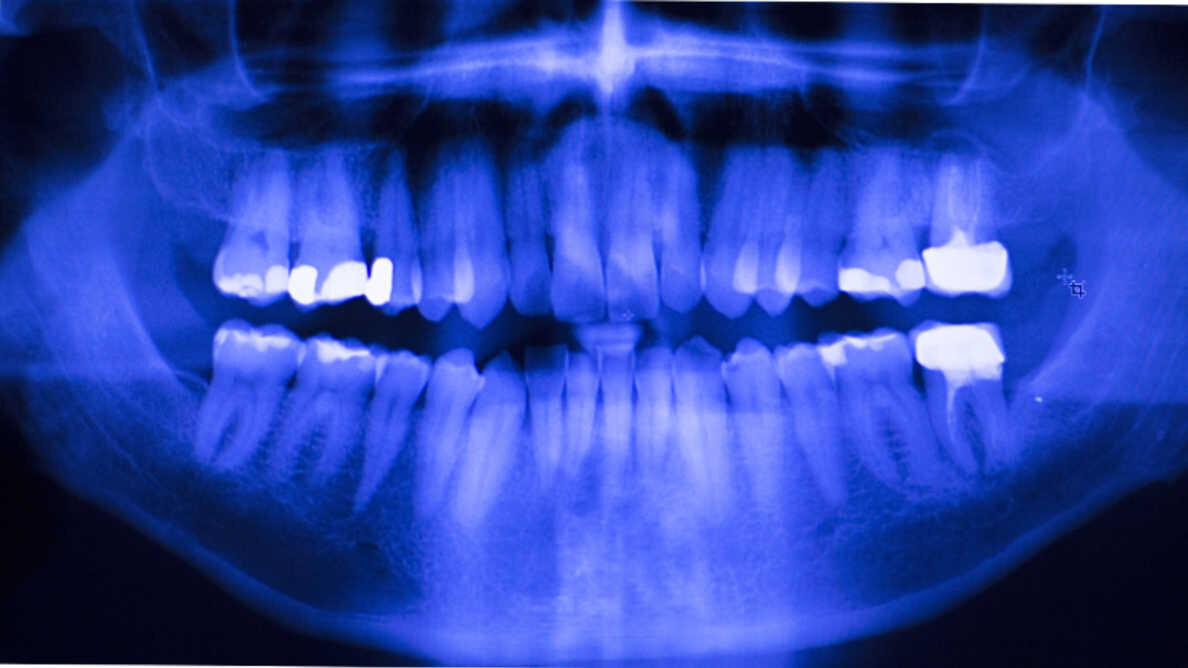

Sur la base du consensus des experts, un nouvel d'aide en ligne permet aux cliniciens d'identifier les options de matériaux et procédures de restauration appropriés. (Photo : edwardolive/Shutterstock)